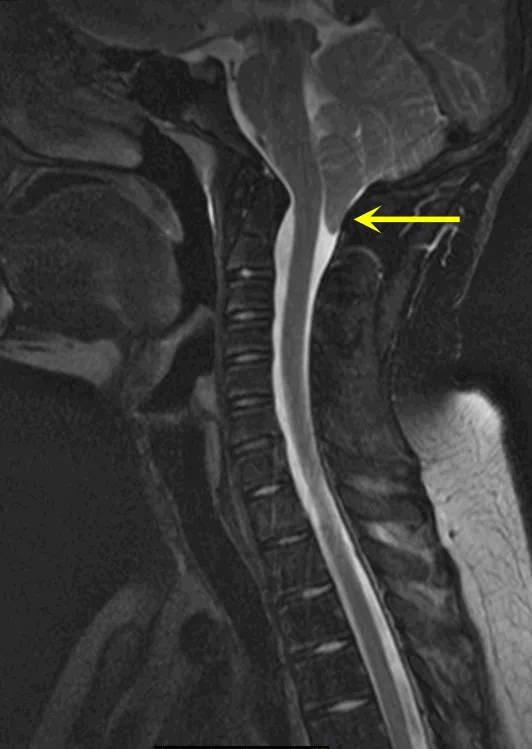

▶▷Chiari I型(CIM-I):最常见的类型,指小脑扁桃体向下延伸至枕骨大孔平面以下,超过枕骨大孔内缘连线5mm,或3-5mm但已表现出相应临床症状者。

幸运的是,约翰的神经系统检查并无异常,也没有出现脊柱侧弯的症状,影像学也确认无脊髓空洞形成。但是由于约翰已表现出头痛的症状,并在Valsalva动作(如用力、屏气、打喷嚏、咳嗽)后加重,这是由于颅内压变化导致的,因此,治疗刻不容缓。